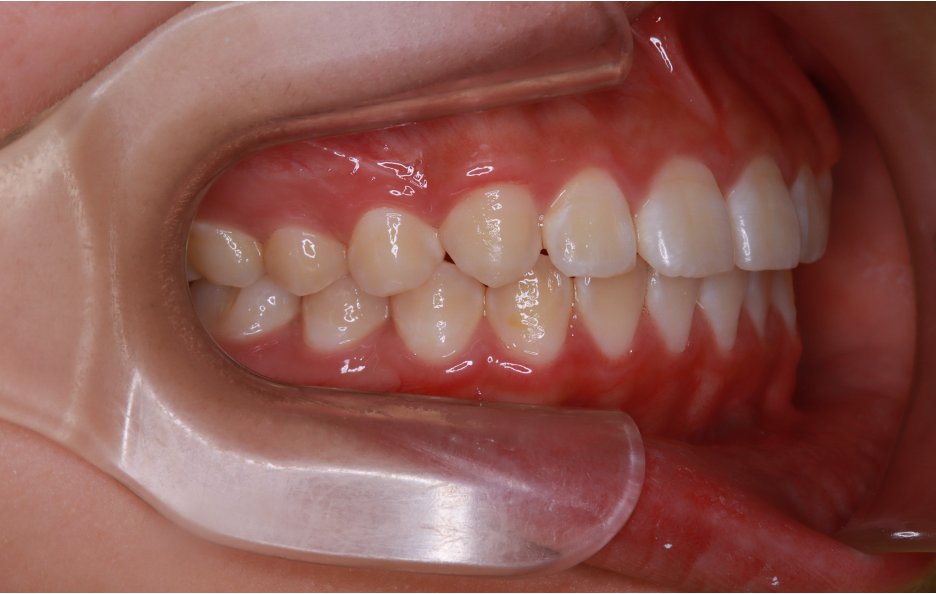

After